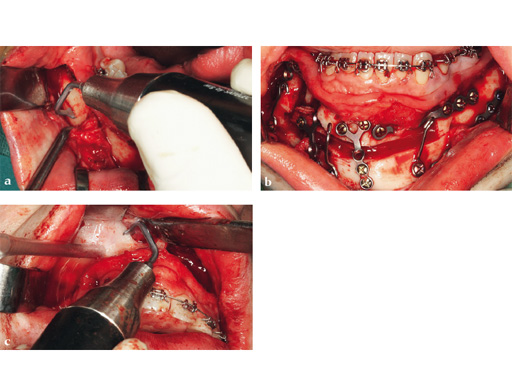

Case 1: A patient after multiple failed chin implants. Here piezosurgery proved to be superior to other oscillating instruments due to the controlled brush-type cutting motion, closeness to vulnerable structures which could be easily preserved, like the mental nerve on both sides, and protection of floor of the mouth vessels after completing the lingual corticotomy.

Case provided by Nils-Claudius Gellrich, Hannover, Germany

Case 2: Complex congenital deformity with distortion of alveolar processes and dentition, resulting in a 3.5 cm nonocclusion in the right maxillomandibular complex. Occlusion is exclusively controlled through the left second premolar to second molar. Piezosurgery was useful in this case due to complex anatomical deformities resulting in atypical positioning of the inferior alveolar canal on the right side. The cramped confines of dental and bony tissues in the deformed anatomy required an adequate type of osteotomy to do a significant yet controlled skeletal movement to overcome the vertical discrepancy intraorally, without changing the outer projection of the mandibular frame.